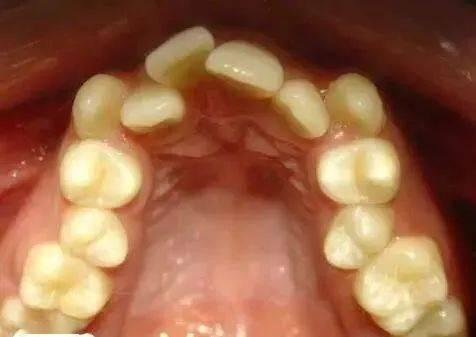

牙齒對(duì)于一個(gè)人來(lái)說(shuō)簡(jiǎn)直是“第二張臉”,畢竟一個(gè)人的牙齒整齊程度往往就會(huì)進(jìn)一步影響面容的美觀,甚至?xí)绊懭穗H交往,因此,不少人為了變好看,都會(huì)選擇外力調(diào)整牙頜形態(tài),改善牙齒功能和健康。牙齒凹陷矯正價(jià)格是多少?一起來(lái)了解一下。

牙齒一個(gè)內(nèi)凹矯正到4000元到8000元左右,具體的費(fèi)用要根據(jù)自己牙齒的情況來(lái)決定。如果牙齒的狀況不是特別的嚴(yán)重容易加重,需要的費(fèi)用會(huì)便宜一些,大概在4000元左右,對(duì)于牙齒矯正的方式比較復(fù)雜,醫(yī)院的級(jí)別比較高,產(chǎn)生的費(fèi)用處于偏高的狀態(tài),可能在8000元左右。矯正牙齒期間需要由專業(yè)的醫(yī)生來(lái)操作,以免產(chǎn)生不良的影響,而且還要注意合理的飲食,不要吃生冷或者吃過(guò)硬的食物,注意口腔的衛(wèi)生,有利于口腔的健康,得到很好的矯正效果。

牙齒一個(gè)內(nèi)凹矯正一般需要1500到4000元不等,具體價(jià)格需要根據(jù)內(nèi)凹嚴(yán)重程度進(jìn)行決定。

如果牙齒內(nèi)凹不是很?chē)?yán)重,則需要的費(fèi)用可能會(huì)較低,大概在1500元左右,但若牙齒內(nèi)凹比較嚴(yán)重,則需要的矯正時(shí)間會(huì)延長(zhǎng),因此需要的費(fèi)用也會(huì)相對(duì)較高,多數(shù)在4000元左右。所以在做牙齒矯正之前,最好提前到正規(guī)的專業(yè)醫(yī)院進(jìn)行詳細(xì)咨詢。

牙齒排列擁擠矯正的價(jià)格大約需要5000-80000元左右,具體的價(jià)格與矯正難度有關(guān)。因?yàn)槊總€(gè)求美者牙齒排列擁擠的情況不一樣,如果擁擠的情況比較嚴(yán)重,矯正的難度相對(duì)更大,價(jià)格要貴一些,大概在80000元左右。反之有些求美者牙齒畸形的情況稍微輕微一些,矯正起來(lái)相對(duì)更容易,價(jià)格自然會(huì)更便宜,大概在5000元左右。此外目前能夠矯正牙齒排列擁擠的方法比較多,比如傳統(tǒng)鋼絲矯正、舌側(cè)矯正、自鎖托槽矯正等都是比較好的,但是每一種方法操作的復(fù)雜程度并不一樣,價(jià)格不相同。